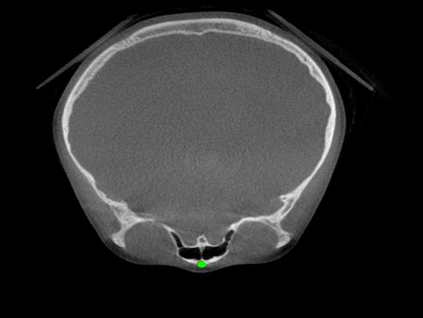

Detecting 3D landmarks on cone-beam computed tomography (CBCT) is crucial to assessing and quantifying the anatomical abnormalities in 3D cephalometric analysis. However, the current methods are time-consuming and suffer from large biases in landmark localization, leading to unreliable diagnosis results. In this work, we propose a novel Structure-Aware Long Short-Term Memory framework (SA-LSTM) for efficient and accurate 3D landmark detection. To reduce the computational burden, SA-LSTM is designed in two stages. It first locates the coarse landmarks via heatmap regression on a down-sampled CBCT volume and then progressively refines landmarks by attentive offset regression using multi-resolution cropped patches. To boost accuracy, SA-LSTM captures global-local dependence among the cropping patches via self-attention. Specifically, a novel graph attention module implicitly encodes the landmark's global structure to rationalize the predicted position. Moreover, a novel attention-gated module recursively filters irrelevant local features and maintains high-confident local predictions for aggregating the final result. Experiments conducted on an in-house dataset and a public dataset show that our method outperforms state-of-the-art methods, achieving 1.64 mm and 2.37 mm average errors, respectively. Furthermore, our method is very efficient, taking only 0.5 seconds for inferring the whole CBCT volume of resolution 768$\times$768$\times$576.